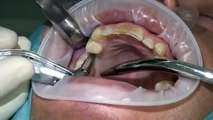

man unterscheidet offene oder geschlossene knochendehnung. zum geschlossenem bone spreading findet ihr hier ein video https://dai.ly/x7tcm84 generell findet ihr fortbildungsvideos in unserer playlist https://www.dailymotion.com/playlist/x6642 sollte ein video / thema nicht dabei sein, dann bitte einfach schreiben und ich werde es ehemöglichst abarbeiten. geschlossenes bonespreading ist immer der offenen variante vor zu ziehen, denn die blutversorgung des knochens bleibt erhalten. nur bei extremen spitzkamm wie in diesem fall ist eine offene vor zu ziehen.